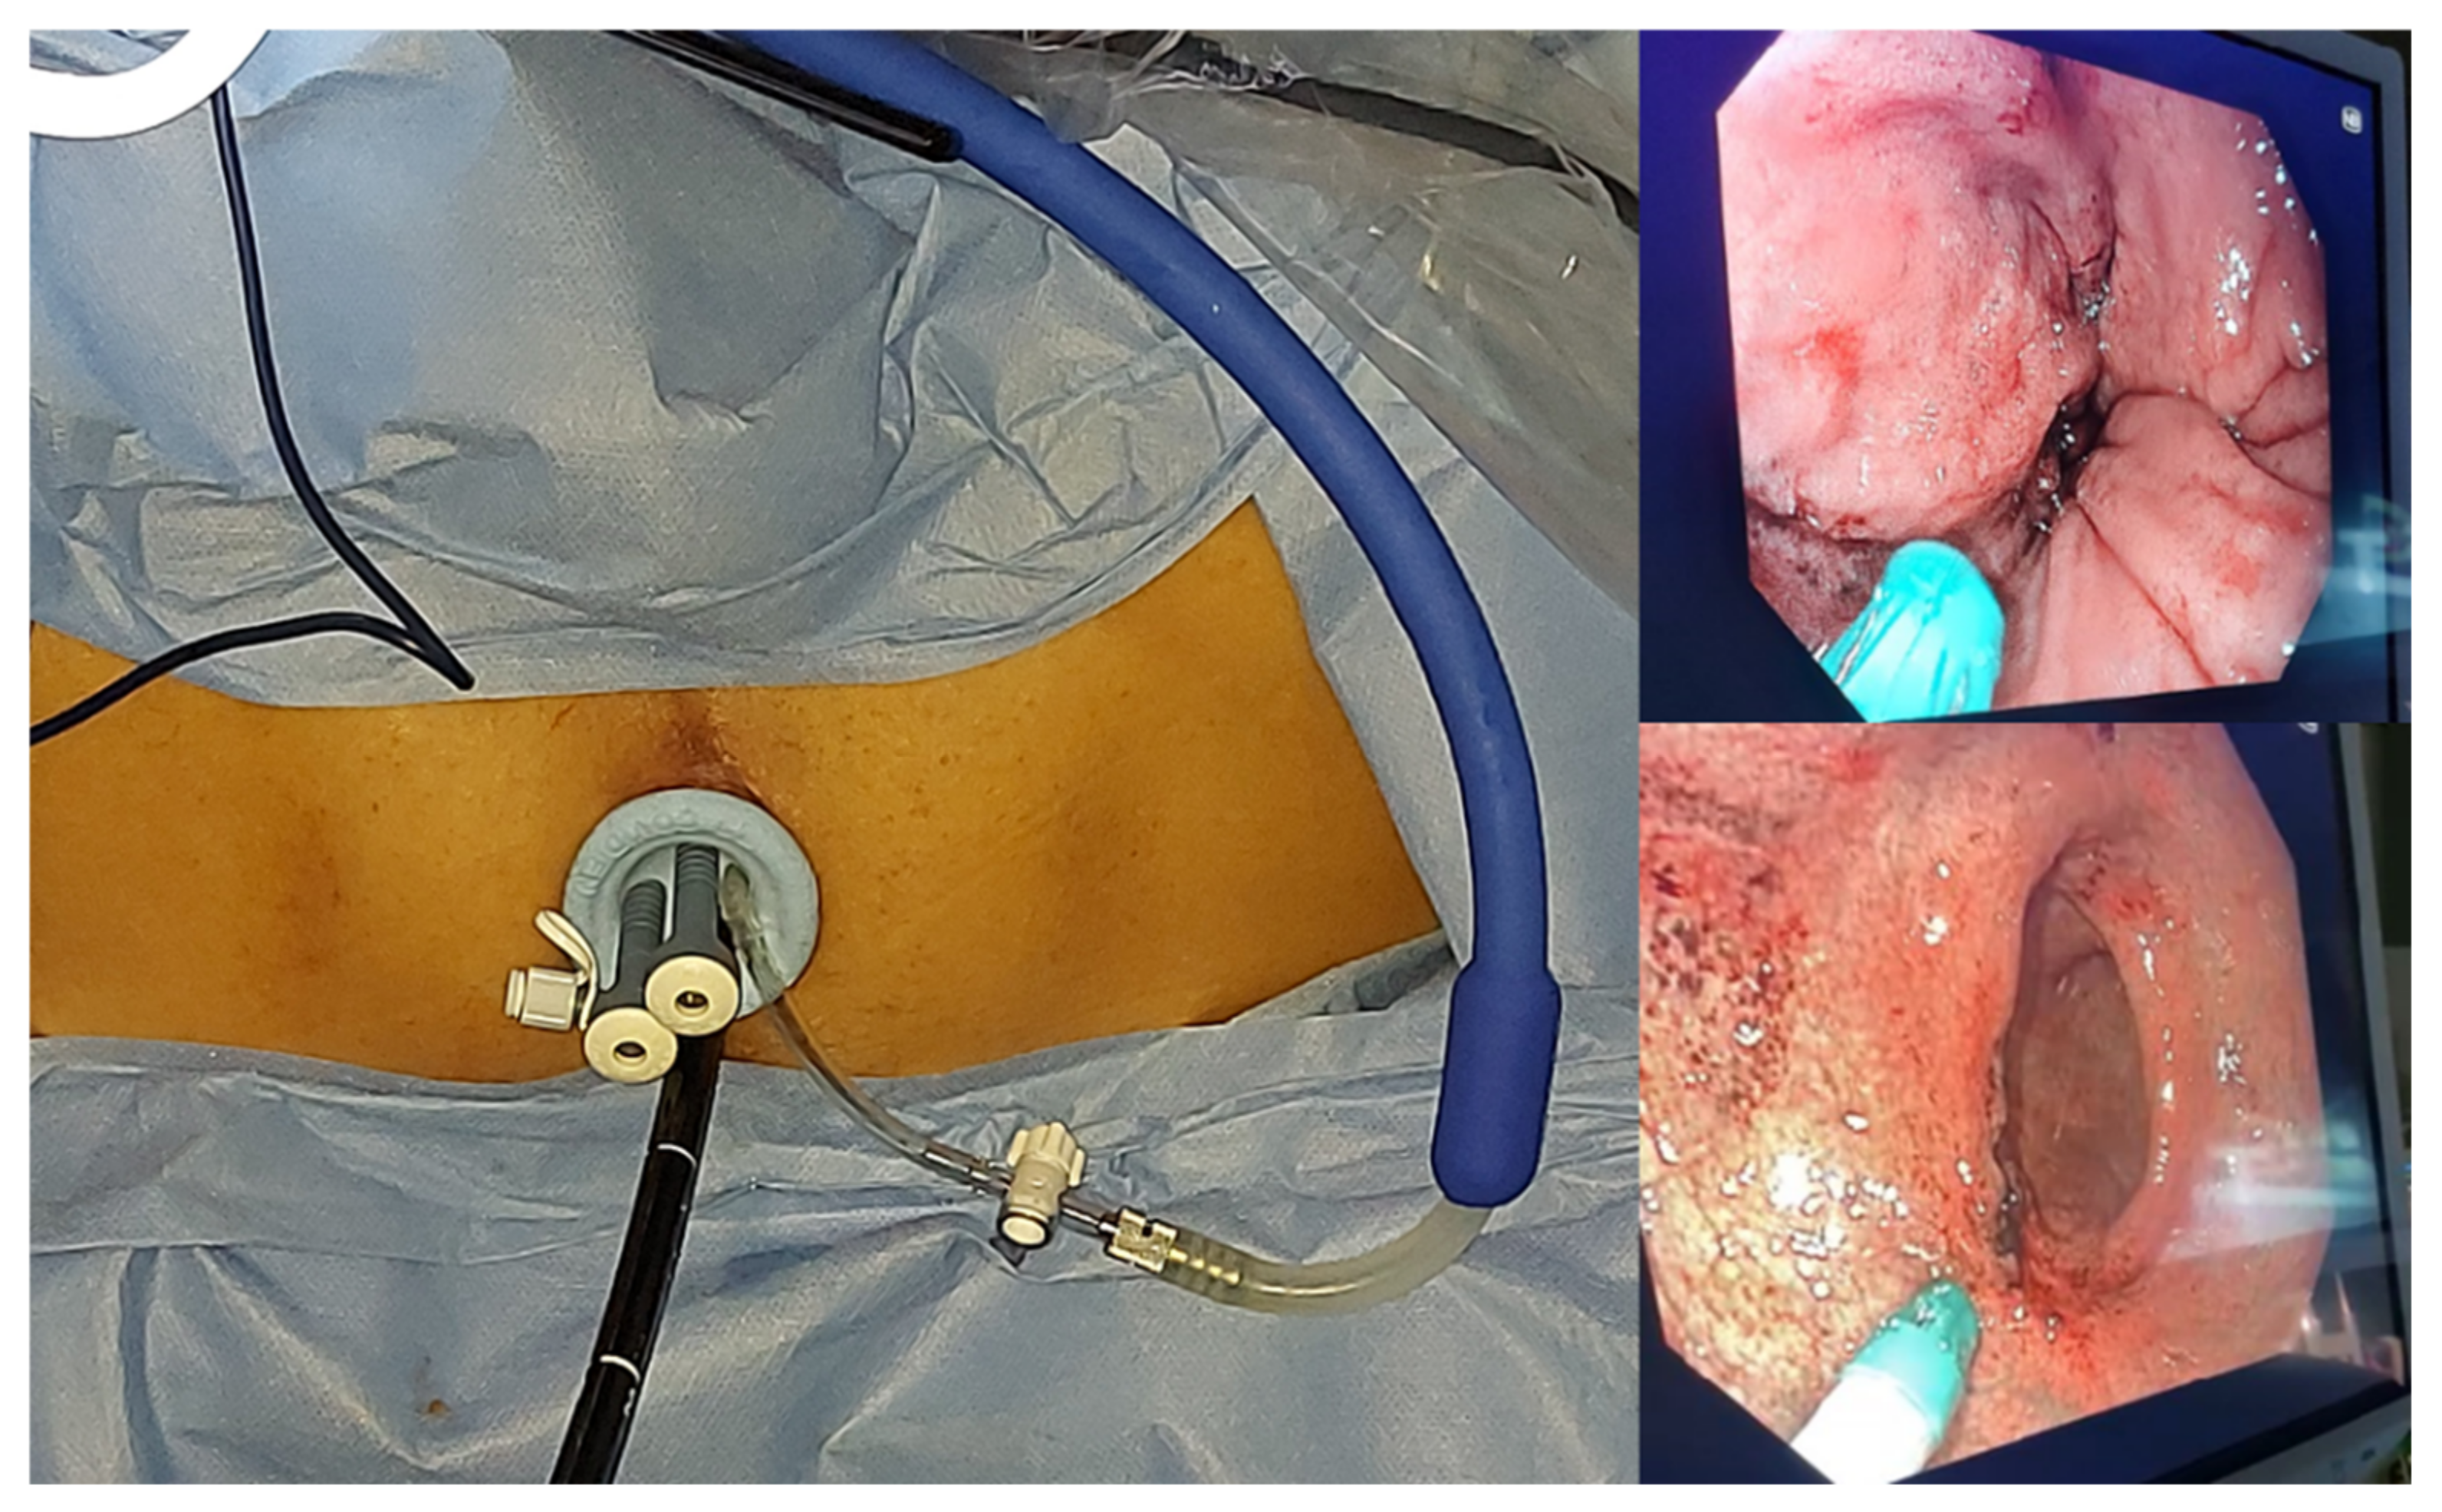

- Rega, D.; Granata, V.; Petrillo, A.; Pace, U.; Sassaroli, C.; Di Marzo, M.; Cervone, C.; Fusco, R.; D’Alessio, V.; Nasti, G.; et al. Organ Sparing for Locally Advanced Rectal Cancer after Neoadjuvant Treatment Followed by Electrochemotherapy. Cancers 2021, 13, 3199. [Google Scholar] [CrossRef] [PubMed]

- Rega, D.; Pace, U.; Niglio, A.; Scala, D.; Sassaroli, C.; Delrio, P. TAMIS for rectal tumors: Advancements of a new approach. Updat. Surg. 2016, 68, 93–97. [Google Scholar] [CrossRef]

| 1 | M 75 years old with major response was treated with ECT 12 weeks after chemo-radiation therapy | Expandable STINGER electrodes | The parietal thickening of the rectum was substantially stable. The lesion still appears in stable disease nine months after ECT. Pain reduction was obtained according to the VAS scale from 2 to 0. |

| 2 | M 66 years old with major response was treated with ECT 12 weeks after chemo-radiation therapy | Expandable STINGER electrodes | CT showed a slight residual thickening of the rectal walls on the side apparently of fibrotic content. The patient reported pain reduction according to the VAS scale from 3 to 0. |